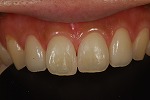

術前

術後